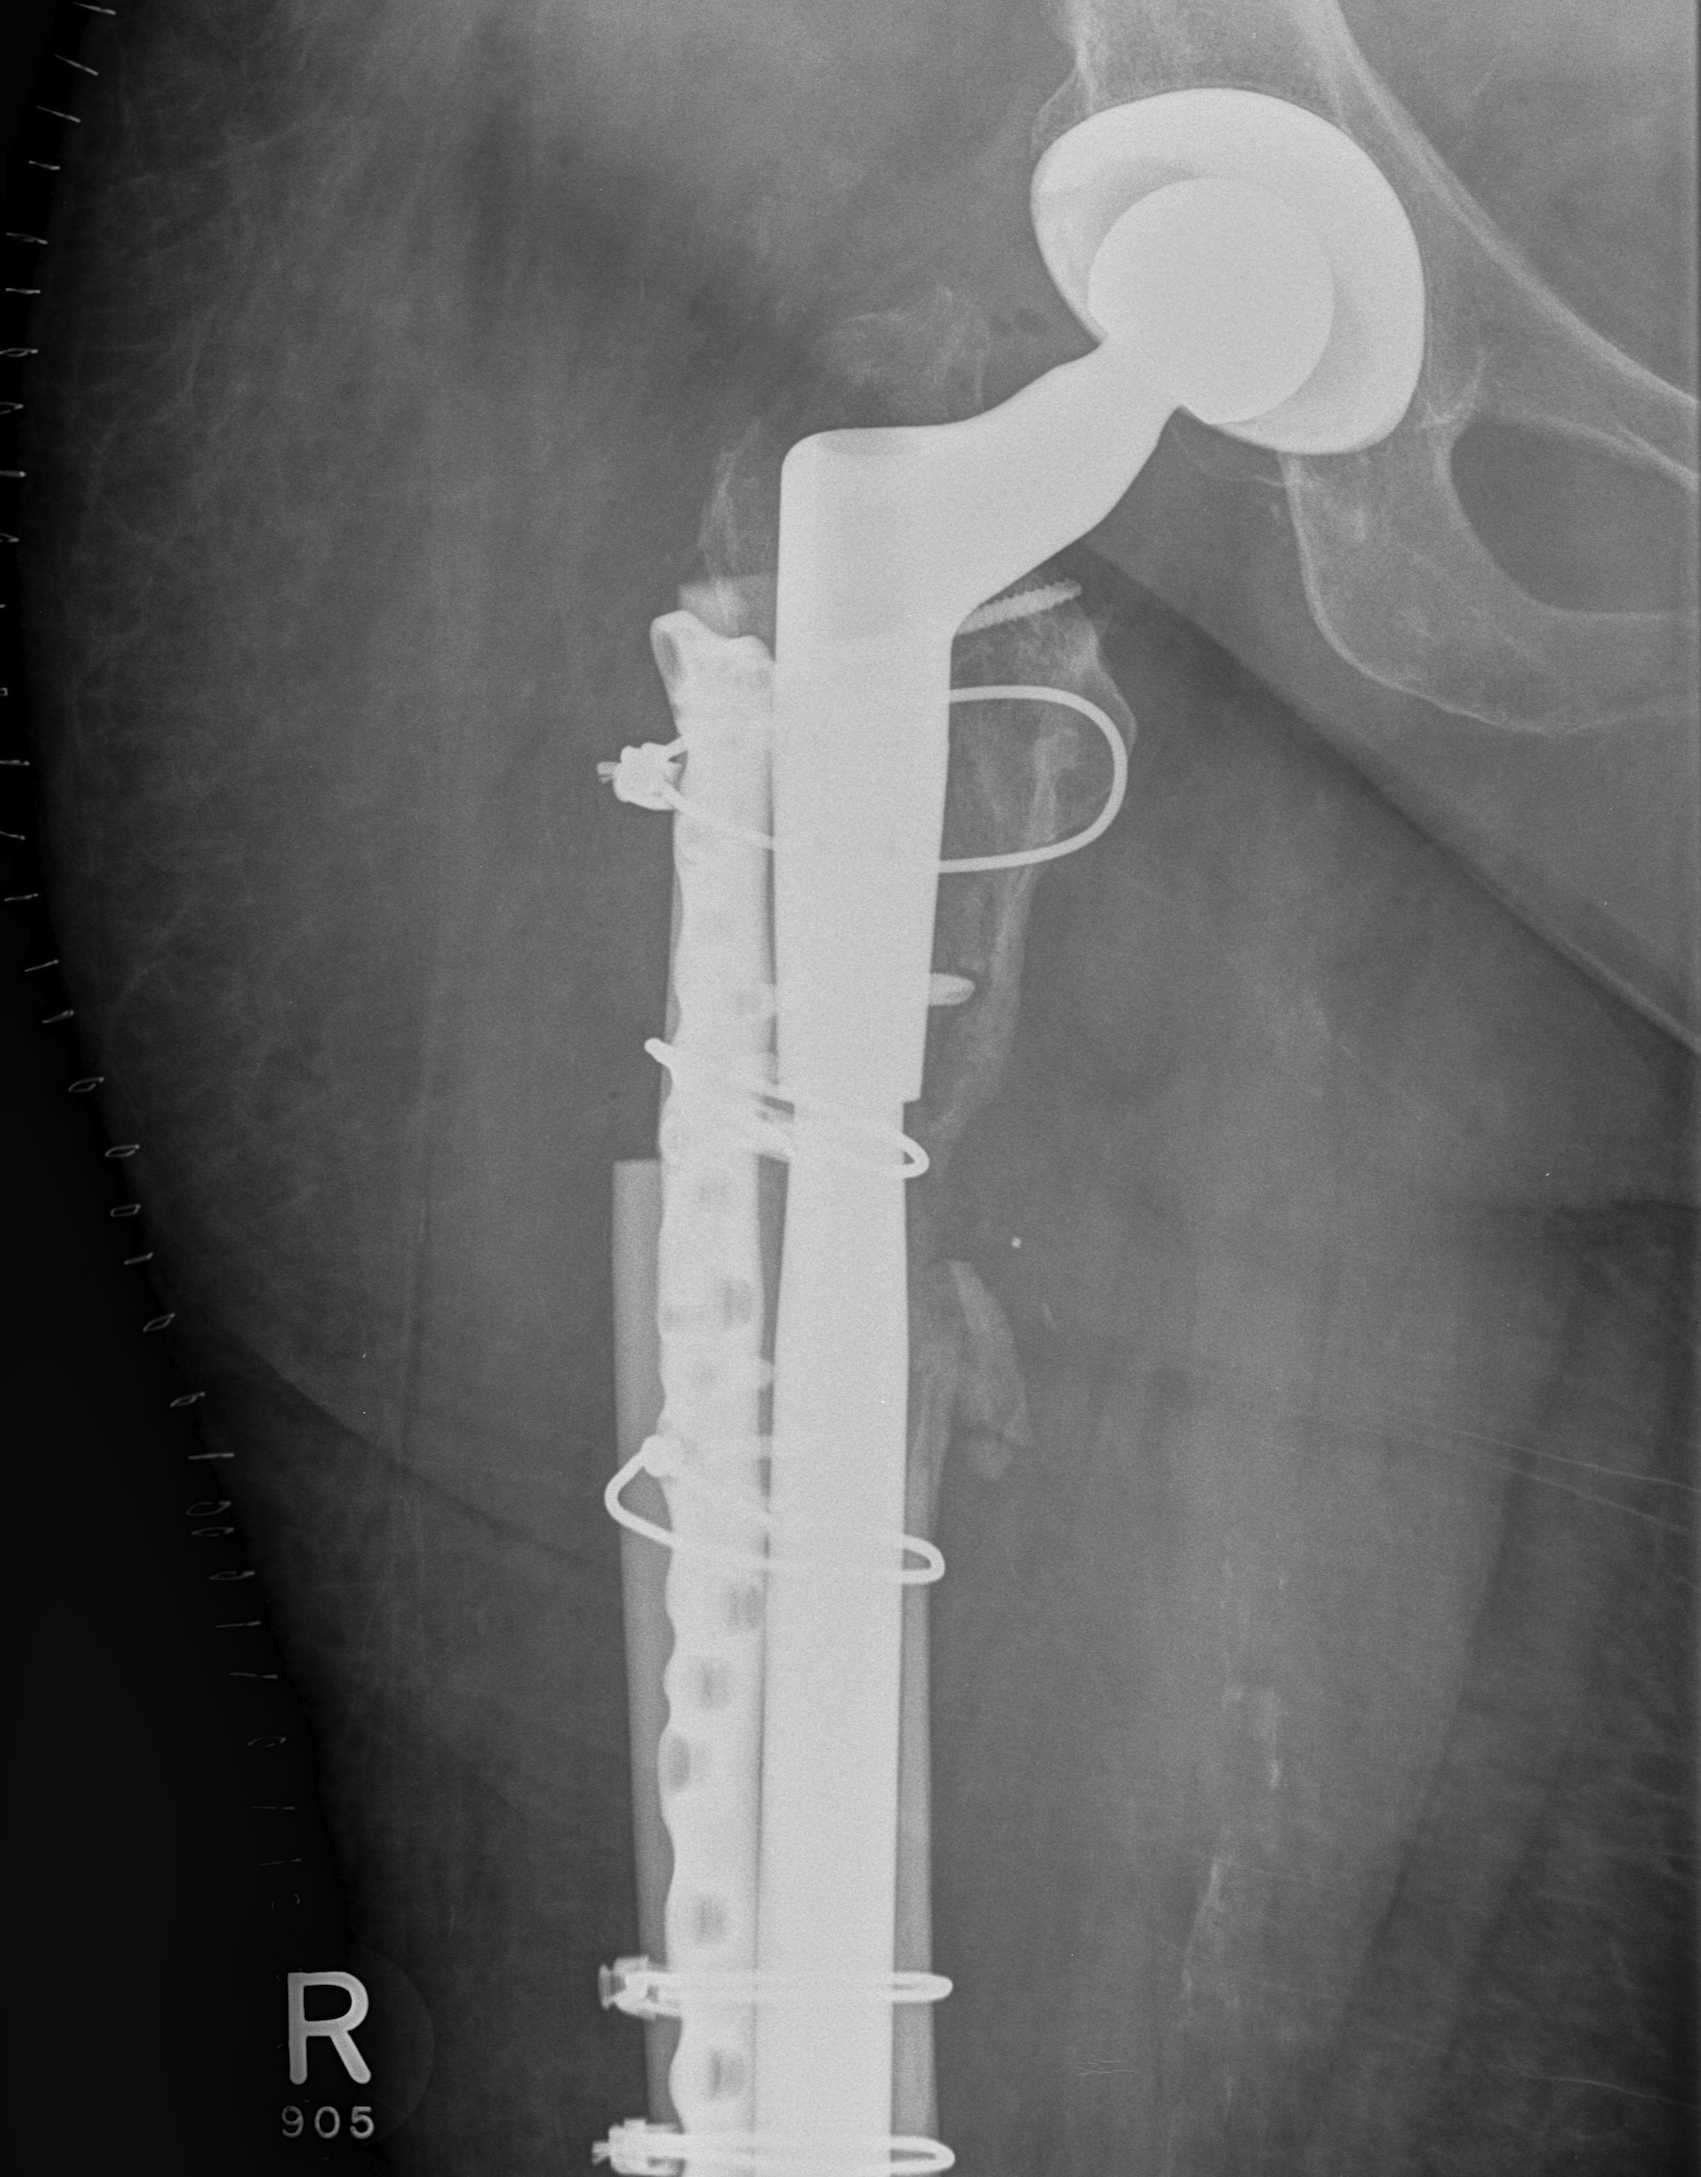

Long stem uncemented revision

Revision uncemented arthroplasty with Zimmer cable plate

Long stem uncemented revision with cortical strut allograft

Long stem uncemented revision with plate + cortical struts